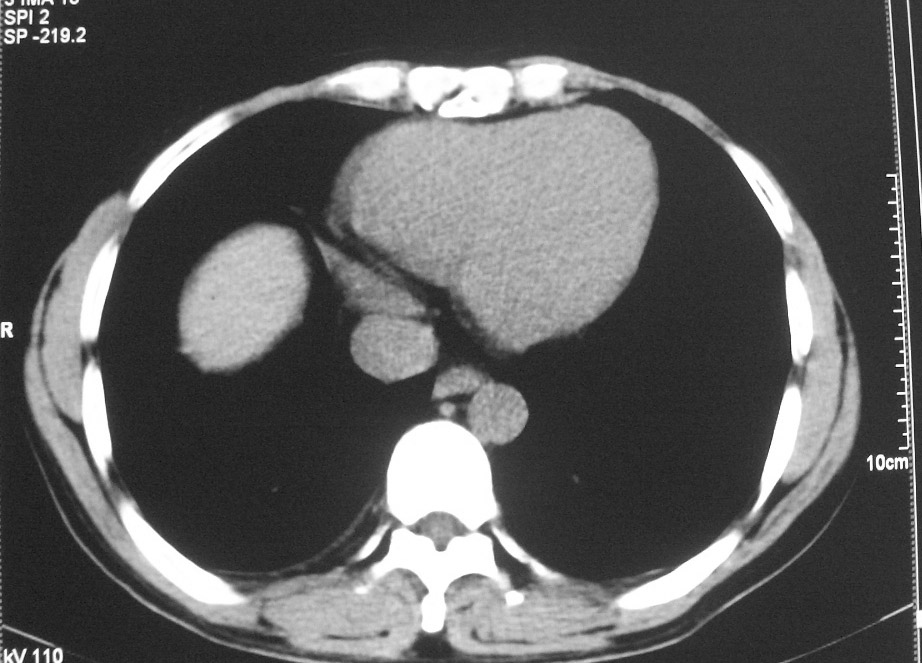

标题: CT5485:[原创]肺部占位请讨论

右肺上叶中央型肺癌并上叶肺不张、纵隔淋巴结肿大

右上叶支气管后壁明显增厚,支持右肺上叶中央型肺癌伴右上叶肺不张、纵隔淋巴结肿大。

右上叶支气管肺癌并右上叶阻塞性不张,右侧少量胸腔积液.

右上叶支气管开口变窄,纵隔见肿大的淋巴结。支持右上叶中心型肺癌并右上叶不张纵隔淋巴结肿大。

右肺上叶中央型肺癌并上叶肺不张、纵隔淋巴结肿大.右侧少量胸腔积液。

右上肺中心型肺癌并肺不张,纵膈淋巴结肿大。右侧少量胸腔积液。

右肺上叶支气管后壁增厚,呈鼠尾状狭窄,纵隔内未见明显增大的淋巴结影,考虑为中央型肺癌伴右上肺不张